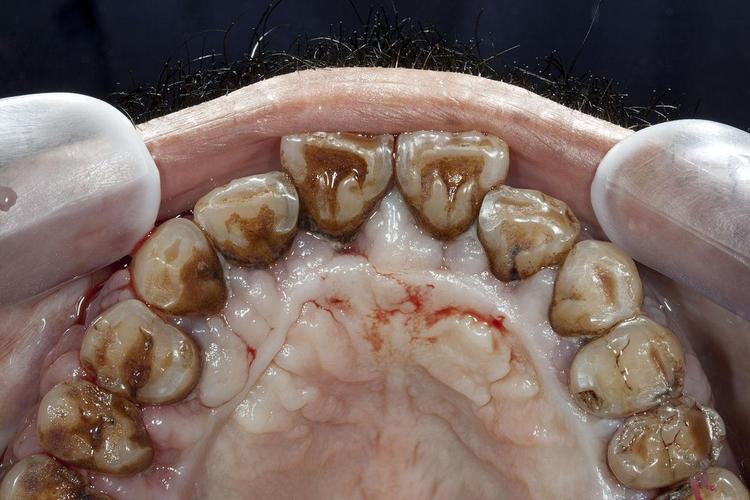

- 牙周炎会导致牙槽骨持续吸收、破坏,骨质变得疏松、薄弱,在这种不健康的、发炎的骨组织上种植,骨结合的质量和成功率会大大降低,种植体可能无法稳固地扎根,甚至松动、脱落。

- 牙周炎意味着口腔内存在大量的致病细菌,尤其是在牙周袋深处。

- 种植手术是一个有创操作,如果牙周炎未得到控制,这些细菌很容易在手术过程中或术后进入种植区域,引起种植体周围炎(一种更难治疗、破坏性更强的炎症,会导致种植体周围骨吸收,最终导致种植失败)或手术创口感染。

(图片来源网络,侵删)- 牙周炎是口腔内的“病灶”,不加以控制,炎症因子可能影响全身健康(与糖尿病、心血管疾病等有相关性)。